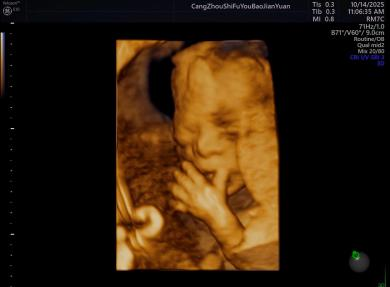

给宝宝的“立体影像”,让产检更安心

科室采用三维/四维超声技术开展胎儿检查,能清晰呈现胎儿面部及身体关键结构的影像,让准父母直观感受宝宝的发育状态。检查中,医生会借助技术对唇腭裂、小下颌等结构异常进行细致观察,同时基于三维容积数据,从多个平面评估胎儿心脏、大脑、脊柱等重要部位,为孕期健康管理提供专业参考。

四维诊断小下颌畸形